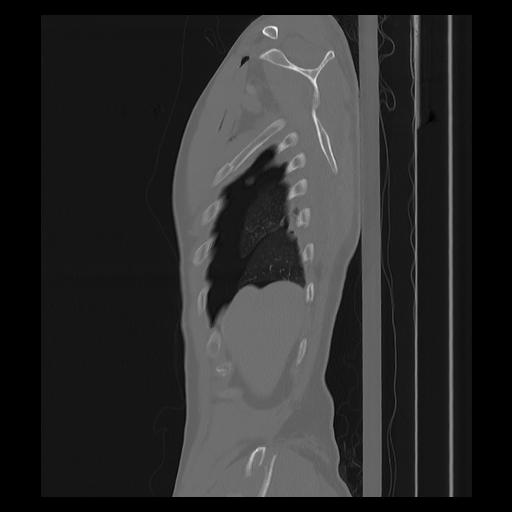

33 PULMON,CE,Sagittal,3.000,PULMON,Sagittal,